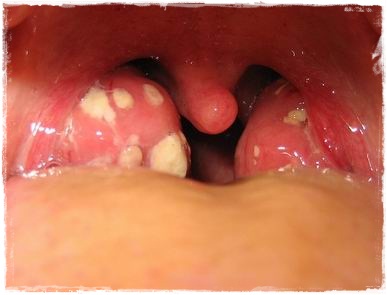

Estafilococus aureus (Cie-10 a05.0)

La Toxiinfección estafilocócica es una de las ETA(s) más frecuentes en el mundo. En 1914 fue identificada la toxina que determina la enfermedad. Staphylococus aureus es un coco gram positivo con superantígenos tóxicos y hemolisina. Entre los primeros se han identificado varios tipos de enterotoxinas (SEs, SEA, SEB, SEC, SED, SEE). S. aureus es muy resistente en el medio ambiente y sobrevive durante períodos prolongados aun en ambientes secos. La enterotoxina termoestable de Staphylococcus aureus es responsable de las ETA(s). La dosis de toxina que provoca enfermedad es 1-5 ug/g alimento.

El hombre es el principal reservorio de S. aureus que se encuentra en la piel y en las vías respiratorias superiores. La contaminación de los alimentos ocurre por contacto directo con la piel del manipulador portador o indirecto a través de las microgotas salivales o el uso de utensilios contaminados. Los animales también son una fuente importante de infección; se destaca la mastitis en los bovinos y ovinos que puede determinar la contaminación de la leche. Los alimentos asociados a brotes son: Jamón, salame, carnes, sandwiches, postres, aderezos de ensaladas.

El período de incubación es 30 minutos-10 horas (promedio 2-6 horas). El período de estado es de comienzo brusco con salivación aguda, vómitos, náuseas, dolor cólico abdominal, diarrea, mialgias, postración, hipotermia, hipotensión arterial. Por tratarse de una enfermedad autolimitada, evoluciona en 1-2 días, se estima que sólo el 10 % de los afectados demanda asistencia. La letalidad es del 0.03 % en población general y del 4 % en niños y ancianos.